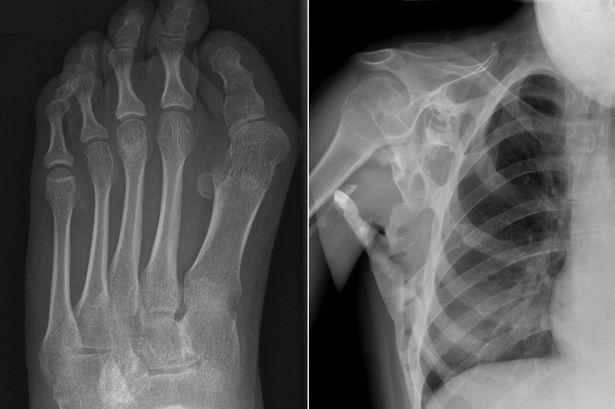

Kas dokusunun kemikleşmesi olarak özetlenebilir.Fibrodysplasia ossificans progresif (FOP) olarak da bilinir. Nadir görülen bir hastalıktır ve genetiktir. Kemikleşmeyen vücut kaslarına örnek olarak kalp kasları, dil, diyafram, düz ve göz kaslarını örnek verebiliriz.

Bu hastalık kişinin yaşamsal fonksiyonu için gerekli hareketleri kısıtlamaktadır. Kaslaşan kemiklere müdahale halinde kemikleşme hızının maalesef ki arttığı gözlemlenmiştir.

- Anormal derecede kemik büyümesinin vücut şeklinize yansıması.

Son olarak neden olabileceği komplikasyonlara bakalım. Ağrı, iltihaplanma ve şişmenin yanında ağır vakalarda solunum yolu enfeksiyonlarına ve kalp yetmezliğine neden olabilir.

Birkaç vakada heterotopik kemik de omurgada eğrilere neden olduğu gözlemlendi. Büyüme tarafına bağlı olarak, yan yana veya yukarıdan aşağıya olabilir. Bireyin yürümesini ve günlük rutinlerini yapmasını zorlaştırabilir.